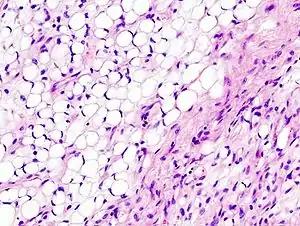

| Histopathology of liposarcoma, H&E stain:[1] - | |

Histopathologically, ALT/WDL tumors are divided into adipocytic/lipoma-like, sclerosing, and inflammatory variants with adipocyte/lipoma-like being the most common. Adipocytic/lipoma-like ALT/WDL tumors consist of lobules of mature fat cells variably intersected with irregular fibrous septa (see the adjacent H&E stained photomicrograph). Sclerosing ALT/WDL tumors, the second most common variant, develop primarily in the retroperitoneal and paratesticular areas; it consists of scattered, atypical stromal cells within a collagenous (i.e. collagen-containing) stromal tissue background. Rare vacuole-containing lipoblasts populate this tissue. Inflammatory ALT/WDL tumors are the rarest variant. they occur most frequently in the retroperitoneum and consists of chronic inflammatory cells, e.g. lymphocytes and plasma cells plus occasional lymph node-like follicles interspersed throughout a tissue background containing fat cells.[14]